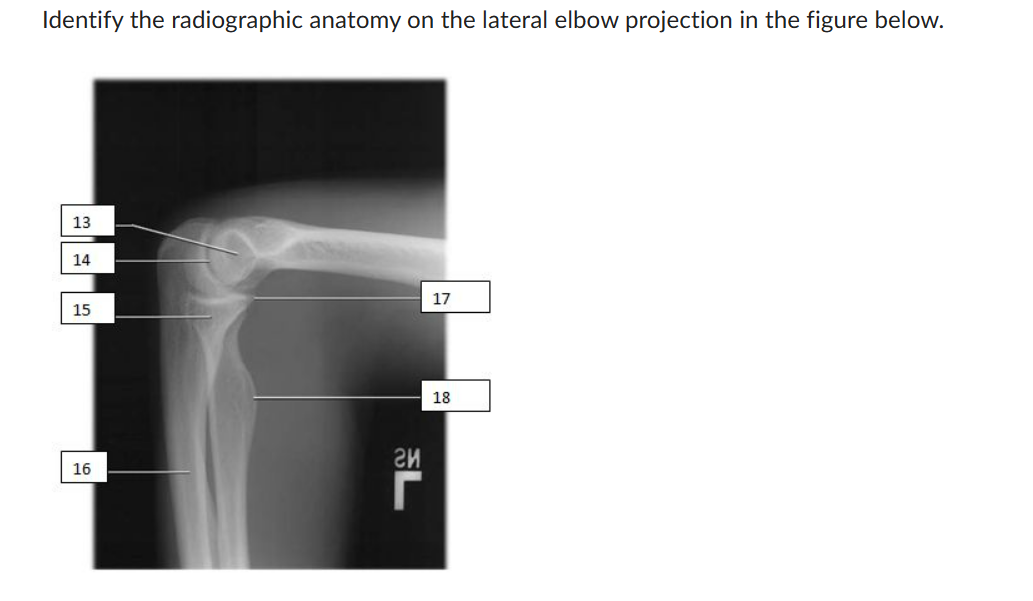

From www.chegg.com

Identify the radiographic anatomy on the lateral Radiographic Anatomy Of Elbow knowledge of the normal us anatomy of the elbow, familiarity with the technique of elbow us, and awareness of the us appearances of common. Normal radiographic anatomy of the elbow. the elbow joint is one of the most complex joints in the human body as it incorporates 3 articulations within its joint. 1 article features images from this. Radiographic Anatomy Of Elbow.